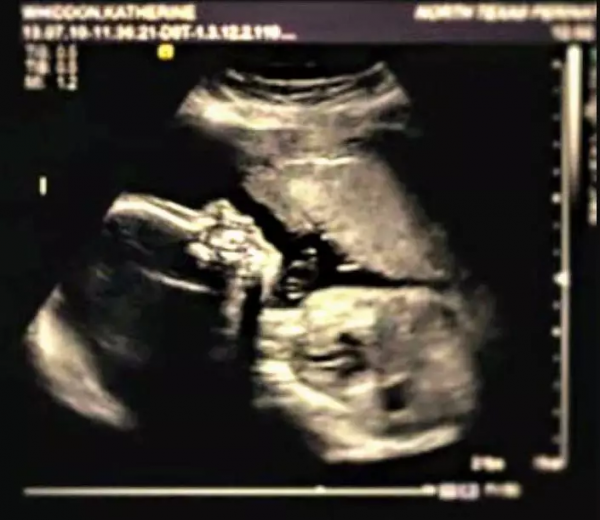

5月,懷孕18周時,她照例去醫院產檢。

“是個男孩兒!”醫生笑著告訴她,凱特也幸福地笑了。

可下一秒,醫生面色凝重,些許遲疑地說:“恐怕事情有些糟糕......”

“我看不到他的胳膊和腿......”

天降噩耗,凱特的寶寶天生殘疾,很有可能活不長久。